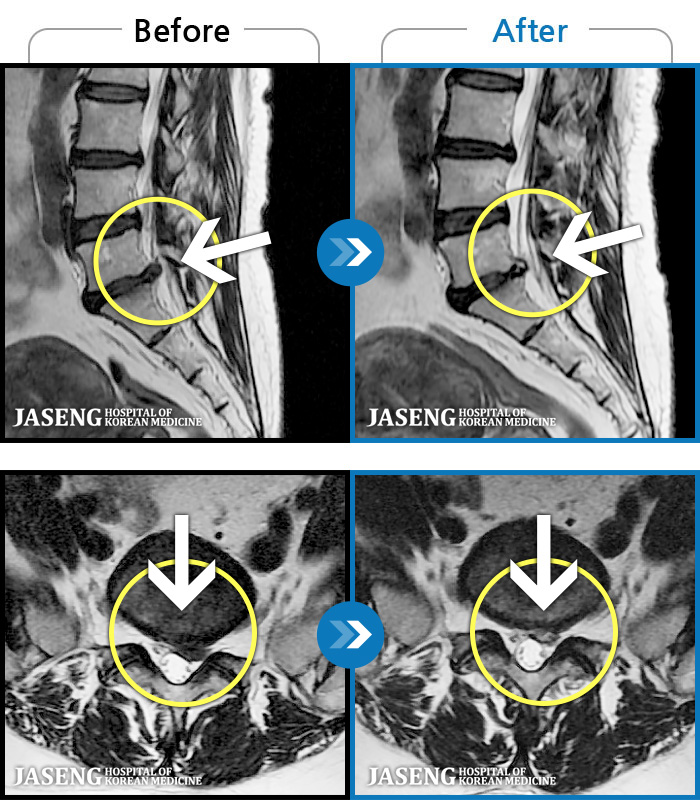

[뱸] 19.11.28~25.05.06